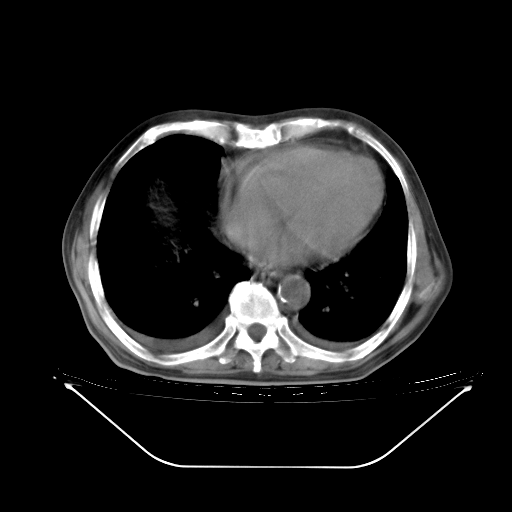

5月9日肺部CT(在4月27日齐鲁医院肺部CT描述部分肺组织磨玻璃样改变,12天后肺组织广泛磨玻璃样改变)

2009年5月9日肺部CT

大致读了系列胸部CT:纵隔窗无明显异常,肺窗:从4、27至今:主要是双肺中下野外带可见毛玻璃样改变,目前处于急性肺泡炎阶段,至于原因考虑1、结替组织或胶原血管性疾病所致?2、恶性疾病如恶组在肺部所致的表现或细支气管肺泡癌?3、药物或其它原因如肺蛋白沉着症所致肺泡炎目前不太可能?总之,明天就去请我院的呼吸科、感染科、血液科和临免专家会诊哈。